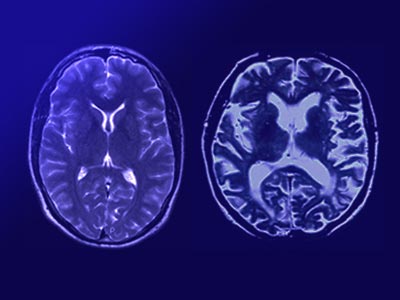

Is It Alzheimer’s or Normal Aging?

Because loss of memory is also a symptom of Alzheimer’s disease, you might worry that these lapses are a sign of something more serious. Alzheimer’s, which affects some 5 million Americans, most of them over 65, is irreversible.